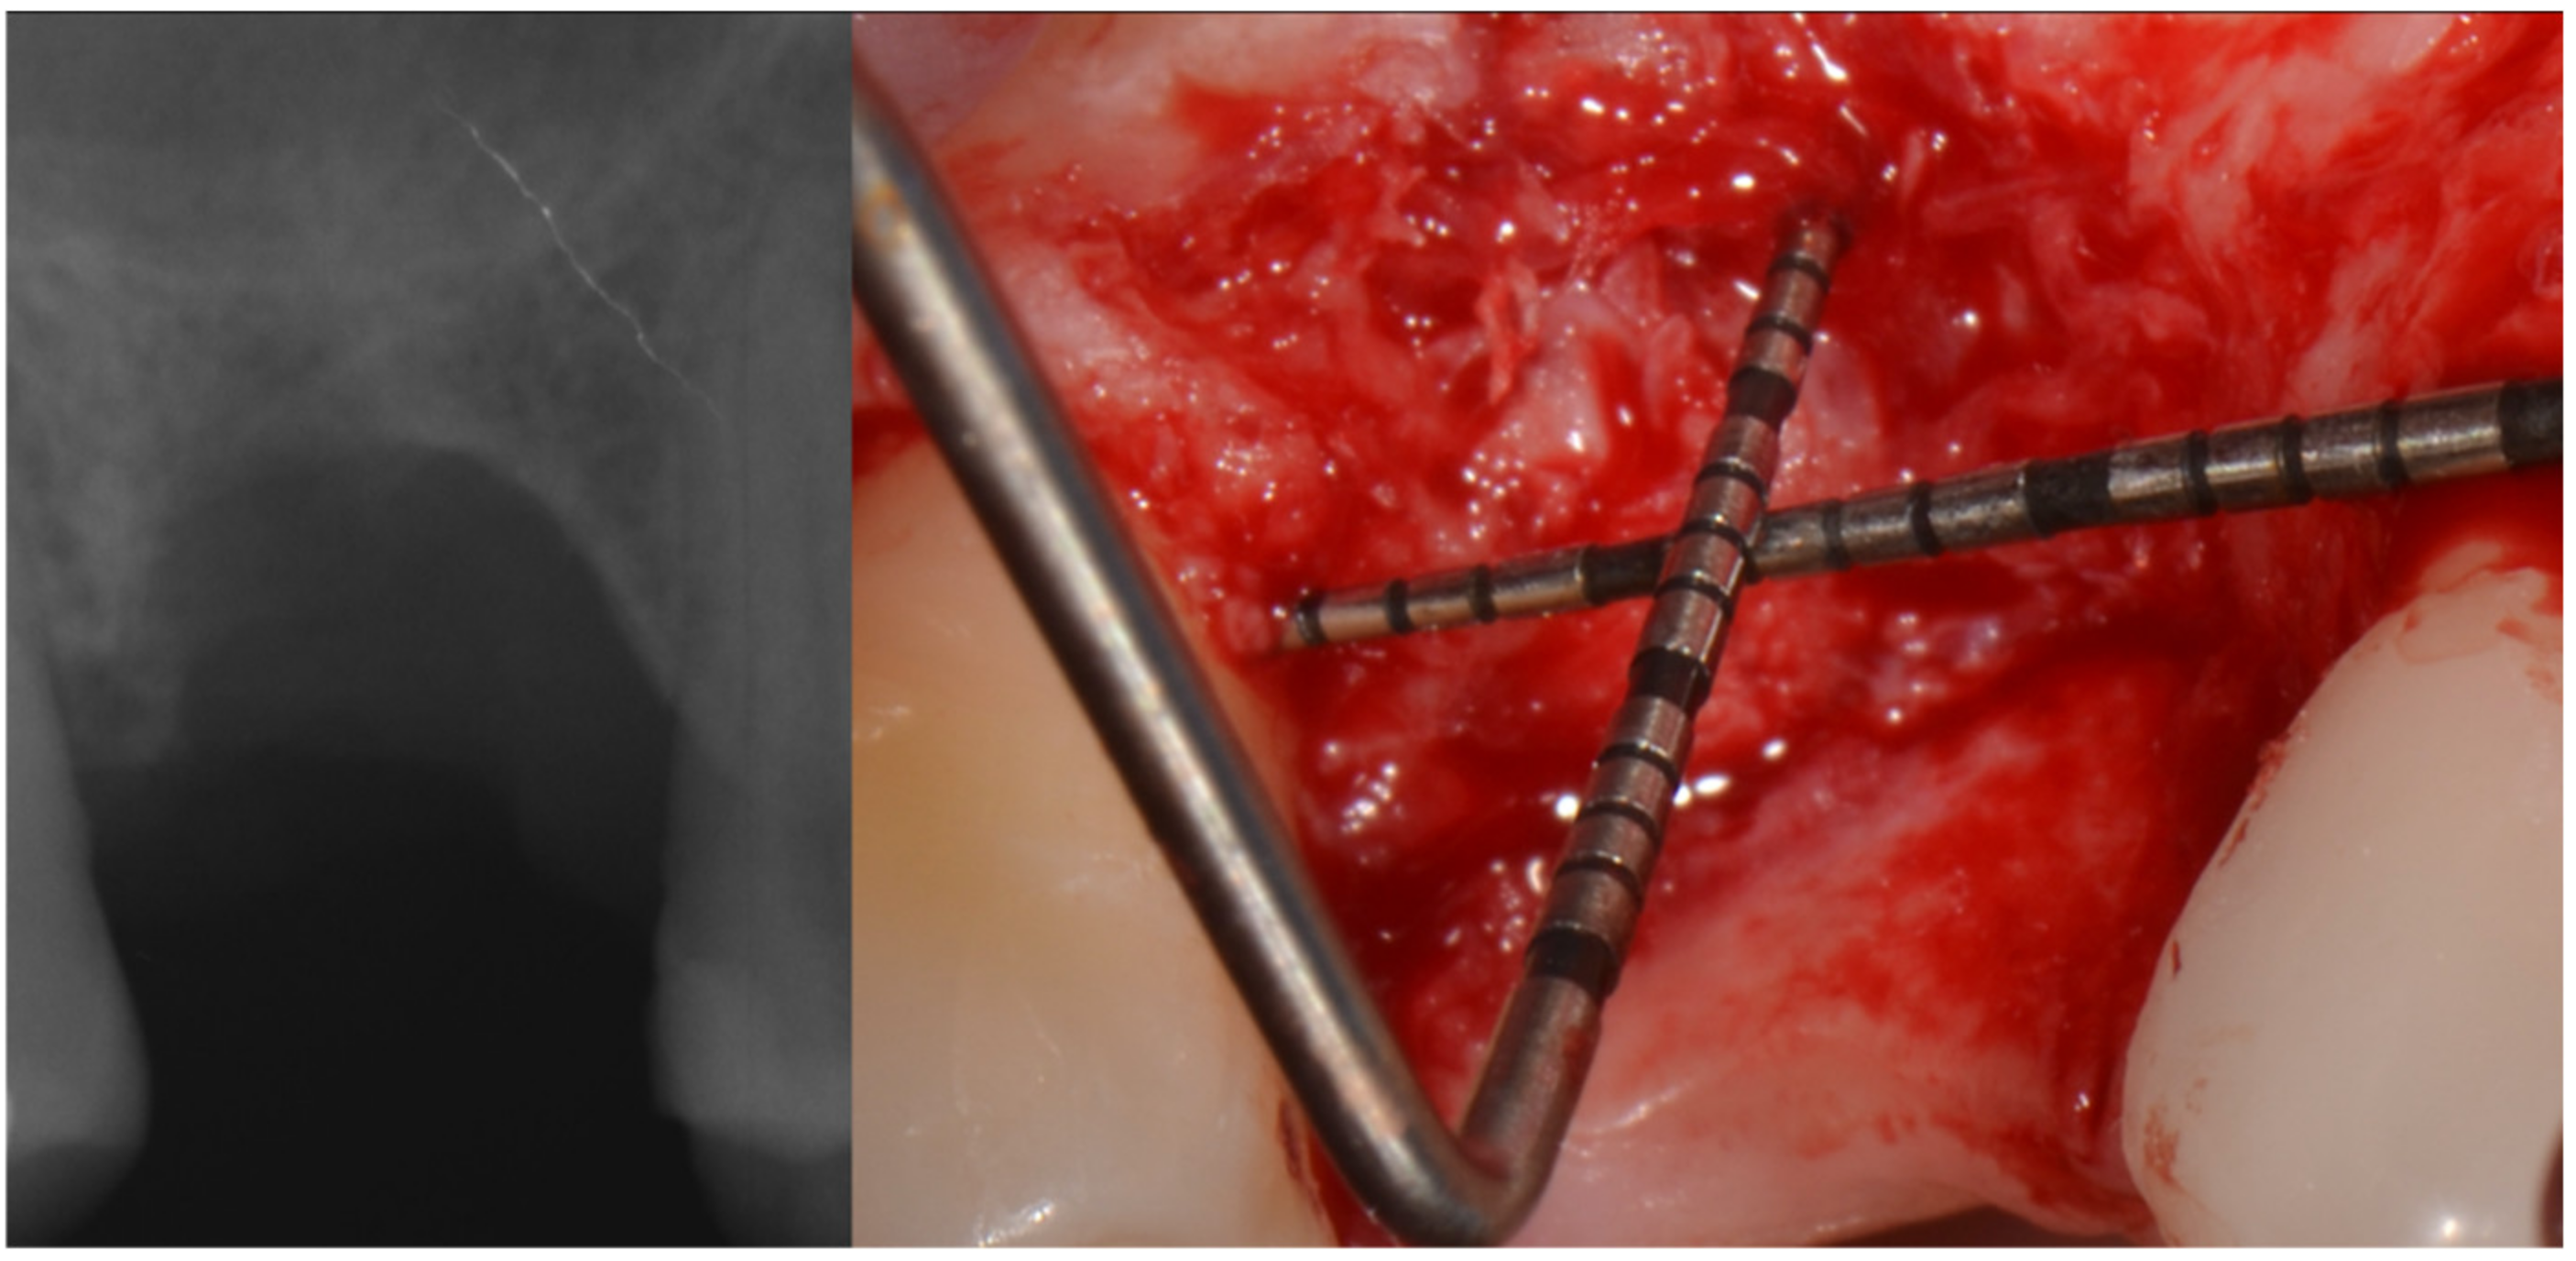

Three months after extraction the site was approached by means of GBR with the cortical lamina technique. Two periodontal probes were crossed to measure 7 mm of the vertical component, and 13 mm of the mesio-distal extension from bone peak to bone peak (Figure 6).

Figure 6.

Rx of the healed defect and its measurement.

The bone lamina was shaped as a saddle, fixed to the buccal bone with two pins, and then, after the area was grafted with a mix of autogenous bone and collagenated xenograft (50–50%), reflected and stabilized under the palatal flap (Figure 7). Flaps were secured with 4.0 resorbable sutures and healing was uneventful.

Figure 7.

Bone lamina in place, arrows indicate the thickness of the lamina (1 mm) inducing both GBR and GTR effect.